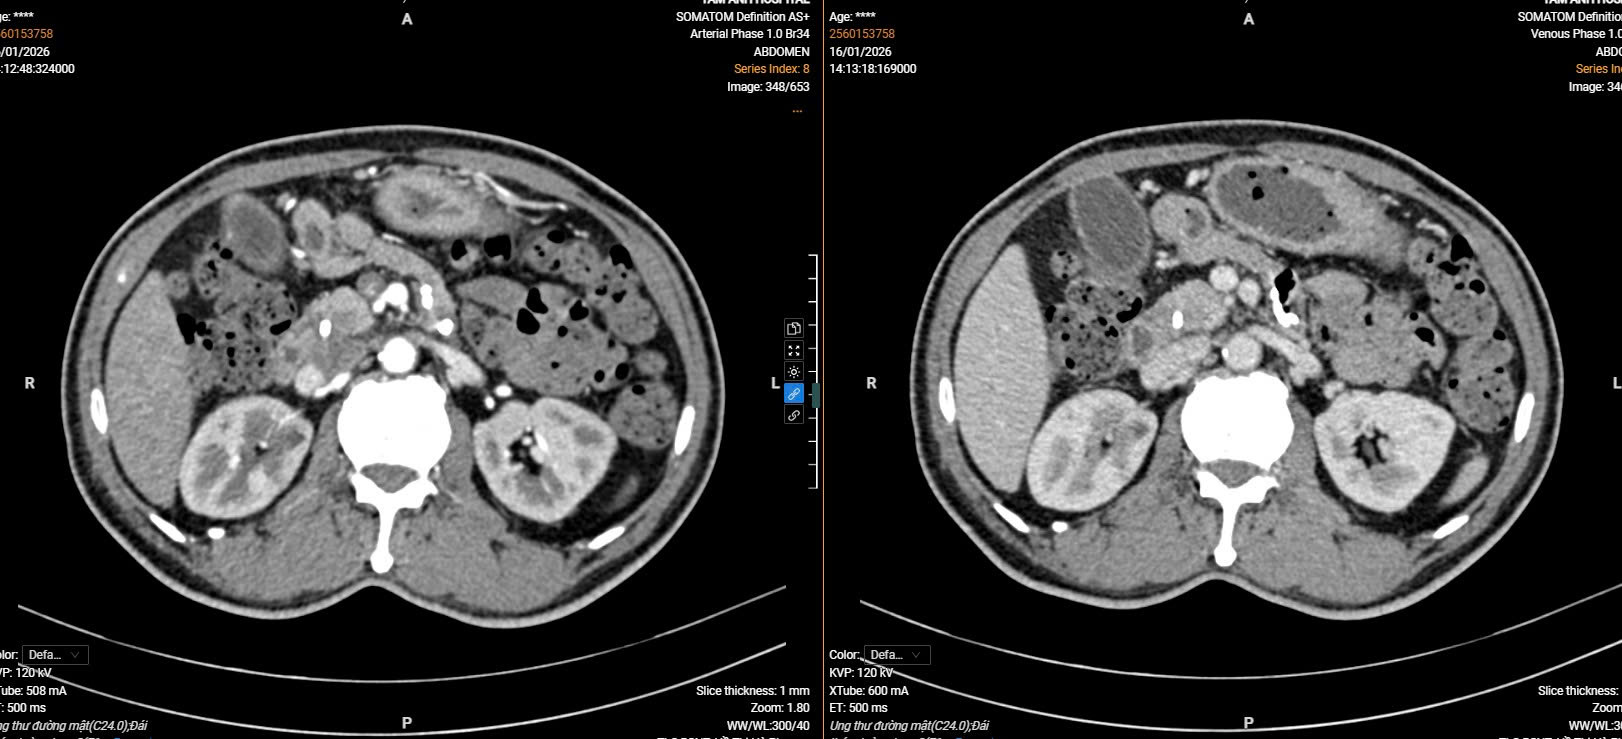

Kết quả cắt lớp vi tính của người bệnh